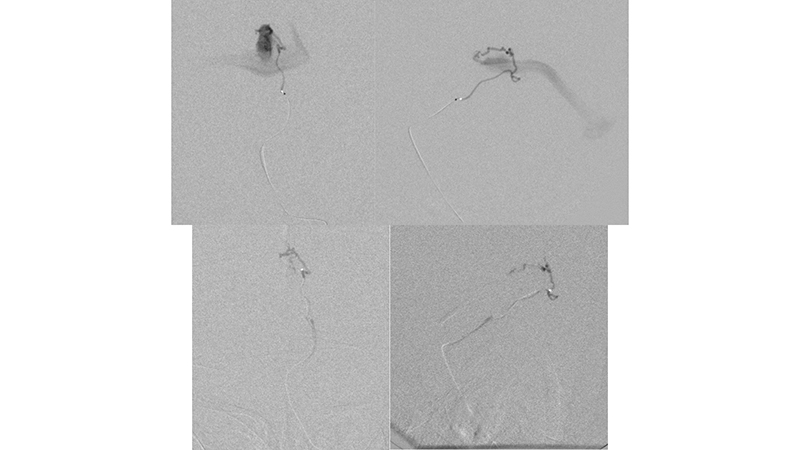

- Καθετηριασμός και εμβολισμός με κυανοακρυλική κόλλα θαλαμοδιατιτραινόντων κλάδων.

- Καθετηριασμός και εμβολισμός με κυανοακρυλική κόλλα υποεπενδυματικών κλάδων.

- Καθετηριασμός και εμβολισμός με κυανοακρυλική κόλλα οπισθιοπλαγίων χοριοειδών κλάδων.

Ως αποτέλεσμα της ανωτέρω αιμοδυναμικής μεταβολής και με δεδομένη την ιακνοποιητική κλινική βελτίωση, αποφασίσθηκε να μην γίνει επέμβαση και ο ασθενής να τεθεί υπό χαμηλού μοριακού βάρους ηπαρίνη λόγω της θρομβώσεως των οπισθίων φλεβωδών κόλπων. - Δύο χρόνια αργότερα, υπερεκλεκτικός καθετηριασμός υποεπενδυματικών και χοριοειδών τροφοφόρων κλάδων από το Ρ1, Ρ2 και Ρ3 των οπισθίων εγκεφαλικών αρτηριών.

- Υπερεκλεκτικός καθετηριασμός υποεπενδυματικών και χοριοειδών τροφοφόρων κλάδων από το Ρ1, Ρ2 και Ρ3 των οπισθίων εγκεφαλικών αρτηριών.